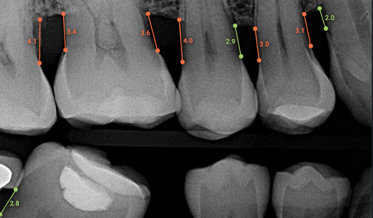

Improving Periodontal Disease Management With Artificial Intelligence

Erin A. Kierce, RDH, MS, MPH; and Robert J. Kolts, DDS, MBA